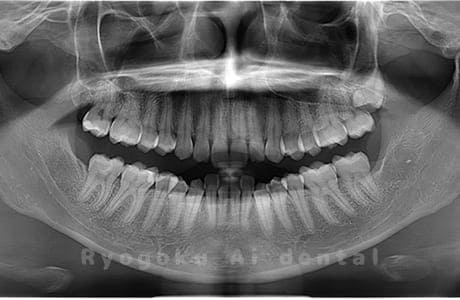

Case02

- 原因

- 下顎の水平埋伏智歯

- 治療内容

- 下顎の水平埋伏智歯を抜歯

<リスク・副作用>

手術後は痛み、腫れ、痺れなどの副作用が生じる場合があります。